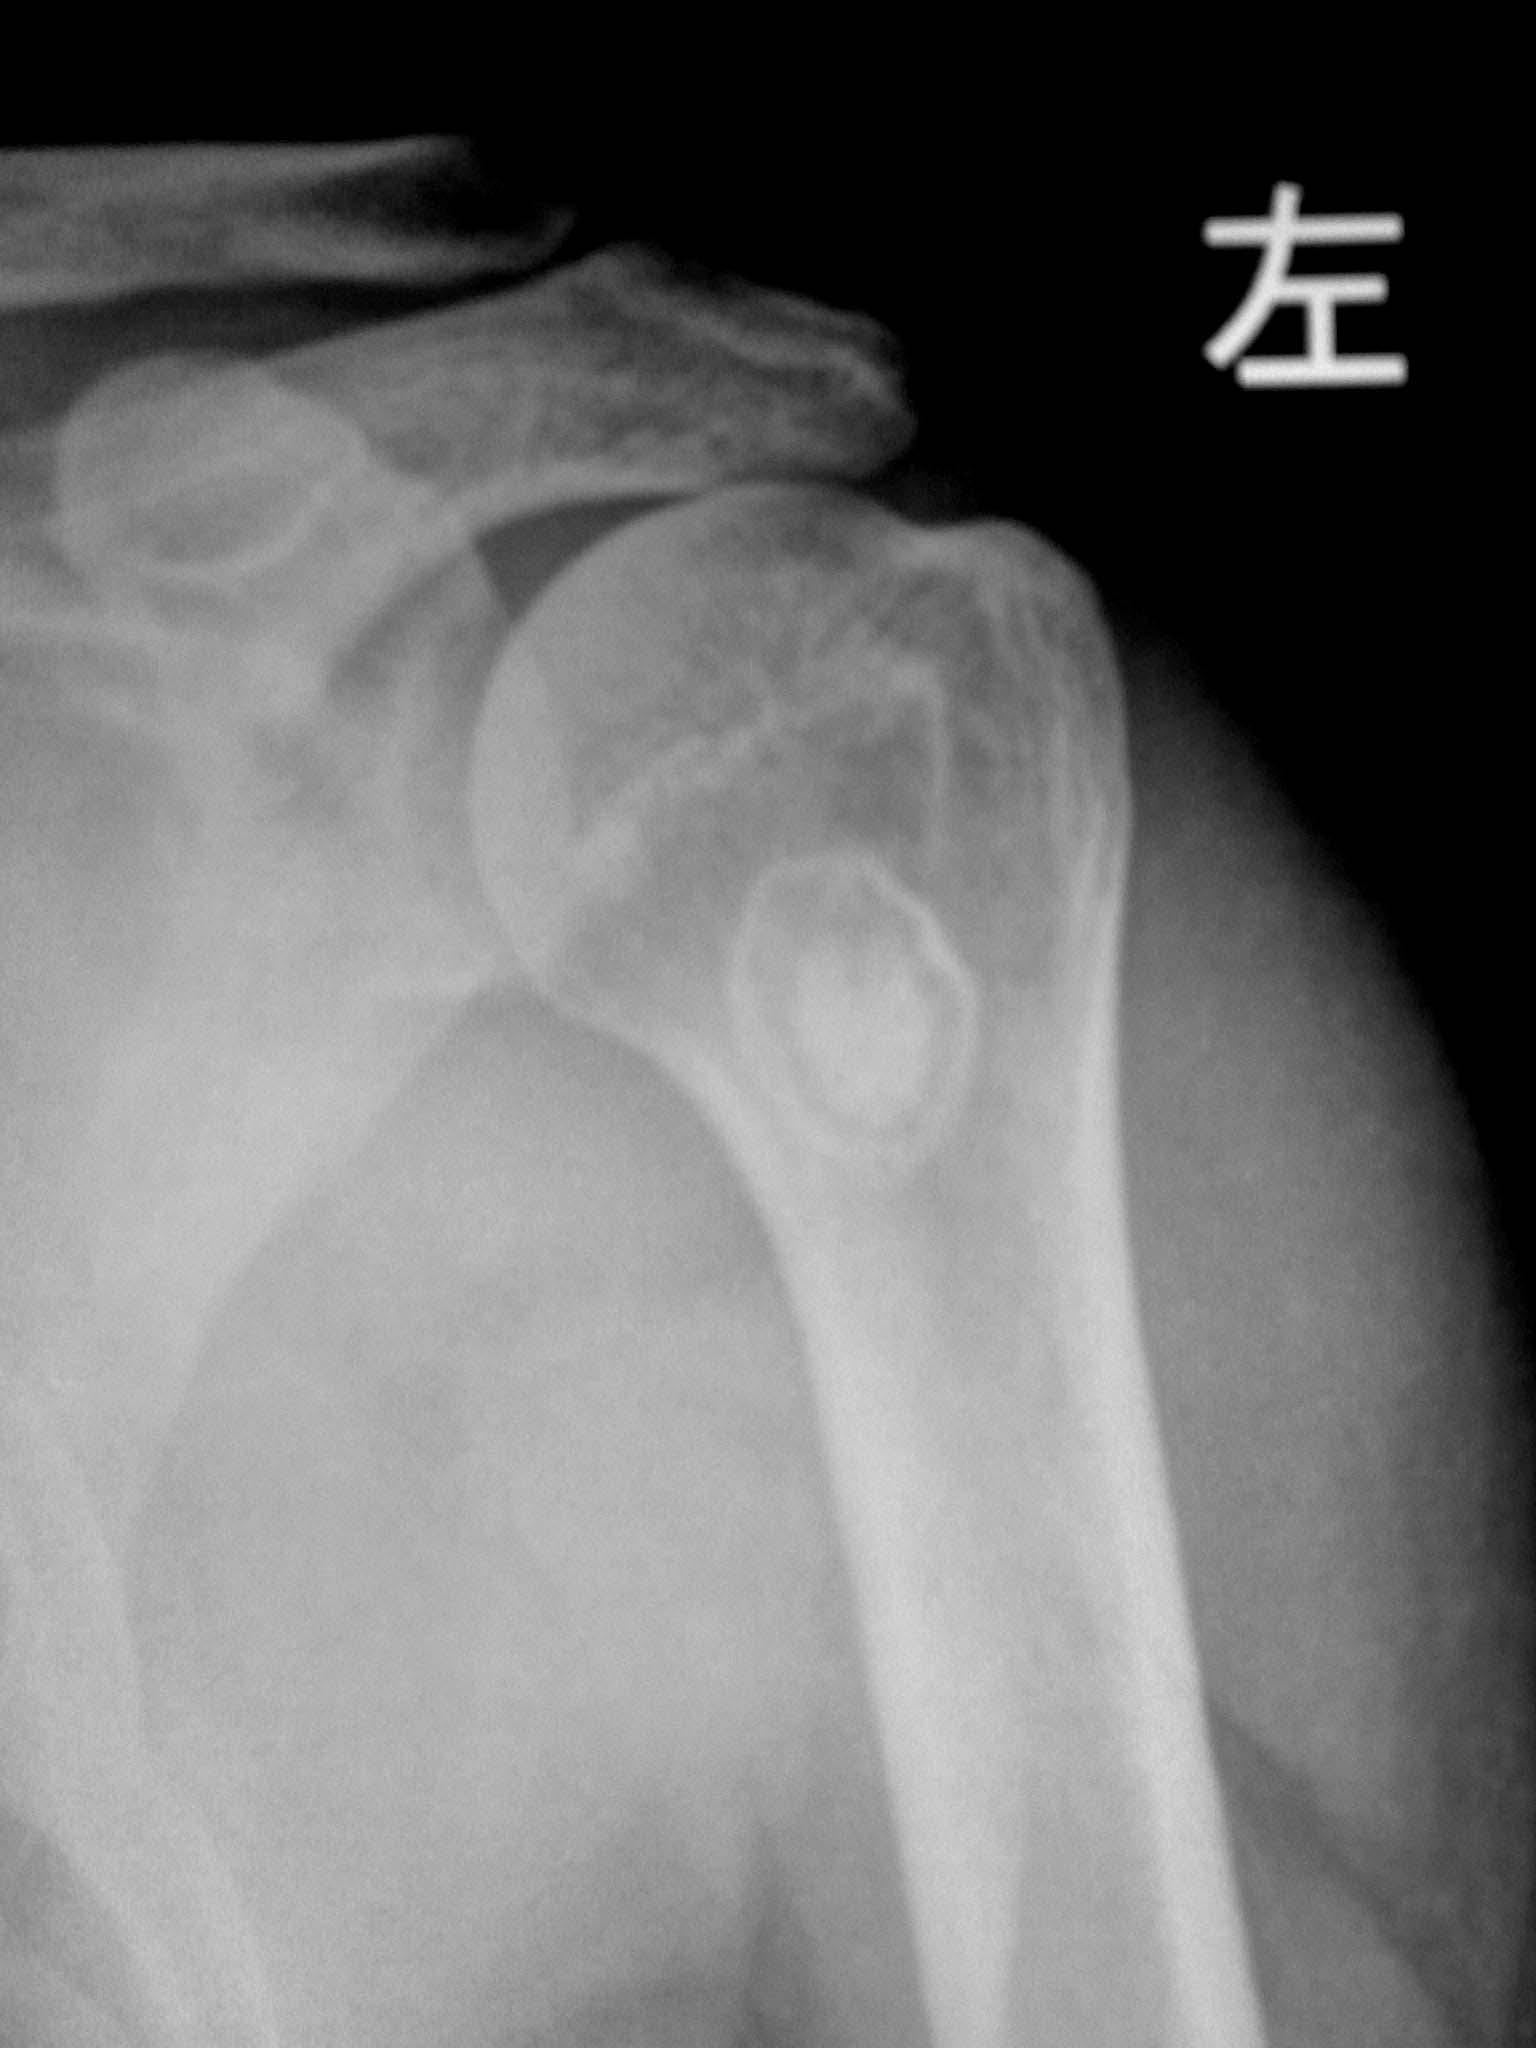

标题: X7640:左肩疼痛。

男性,51岁,左肩疼痛一年,活动不受限。

肱骨上端类圆形低密度影,边缘硬化,其中可见圆形高密度影。我考虑骨化性纤维瘤可能性大,不除外局限性硬化性骨纤

左肱骨上端髓腔内可见环状低密度影,周边硬化,内见圆形高密度影,肱骨皮质及软组织未见异常,支持考虑内生性软骨瘤可能性大,骨梗死??